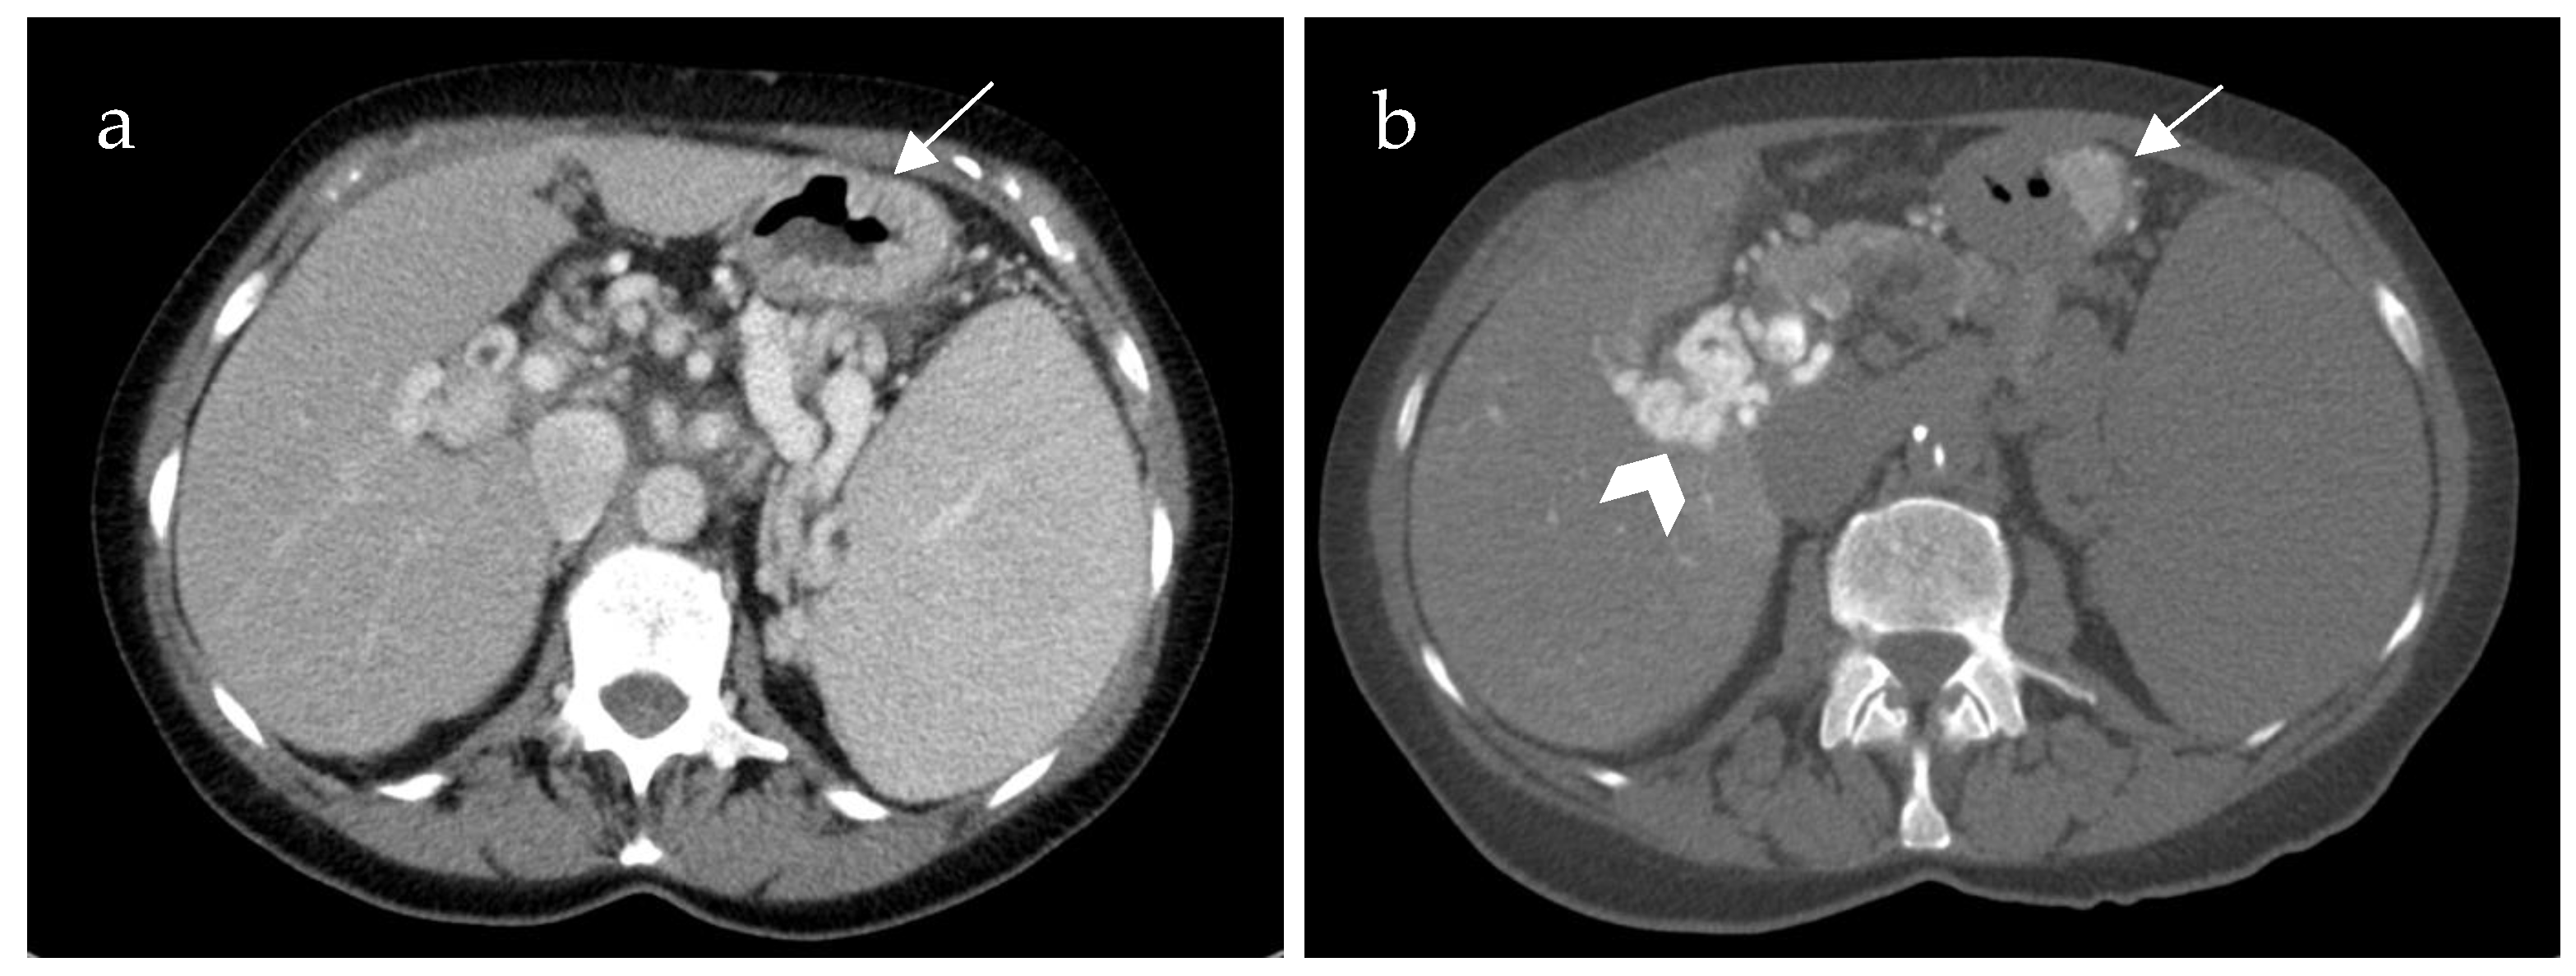

Inflow into esophageal, gastric and small bowel varices differed significantly between patients with PVCT (p = 0.021, p = 0.016 and p = 0.031, respectively) compared to patients without PVCT. In patients with PVCT, esophageal varices were fed solely by the SV in 75% (n = 9, example shown in Figure 3), solely by the mesenteric vein system in 8% (n = 1) and by both systems in 17% (n = 2, example of this rare case shown in Figure 4). Patients without PVCT showed a more equal distribution of inflow hemodynamics: esophageal varices were fed by solely the SV system in 22% (n = 2), by solely the SMV system in 22% (n = 2) and by both systems in 56% (n = 5, example of this is shown in Figure 5). In patients without PVCT, gastric varices were fed by the SV (22%, n = 2), by the SMV (11%, n = 1) or both (22%, n = 2). In contrast, 59% of the patients with PVCT (n = 7) showed gastric varices which were fed only by the SV. In 33% of cases (n = 4), both the SV and SMV drained into gastric varices. No inflow into gastric varices solely from the SMV was detected. These results were statistically significant (p = 0.016).

Figure 4. Computed tomography mesenterico-portography of a 24-year-old male patient with portal hypertension and portal vein thrombosis involving the confluence. Axial (a) and coronal (b) image after contrast injection into the superior mesenteric artery shows large contrasted periesophageal varices (white arrow) fed by the mesenteric system.

Figure 5. Patient of 61 years of age with portal hypertension and isolated portal vein thrombosis without involvement of the confluence. The computed tomography spleno-portography (a) shows contrasted esophageal varices (EV). The computed tomography mesenterico-portography (b) also shows contrasted EV. The EV are therefore fed by both the superior mesenteric vein and the splenic vein (white arrows). Contrast-enhanced computed tomography (c) after intravenous injection of contrast medium shows low contrast of all tissues and vessels. It does not reveal clearly distinguishable varices in the esophagus.